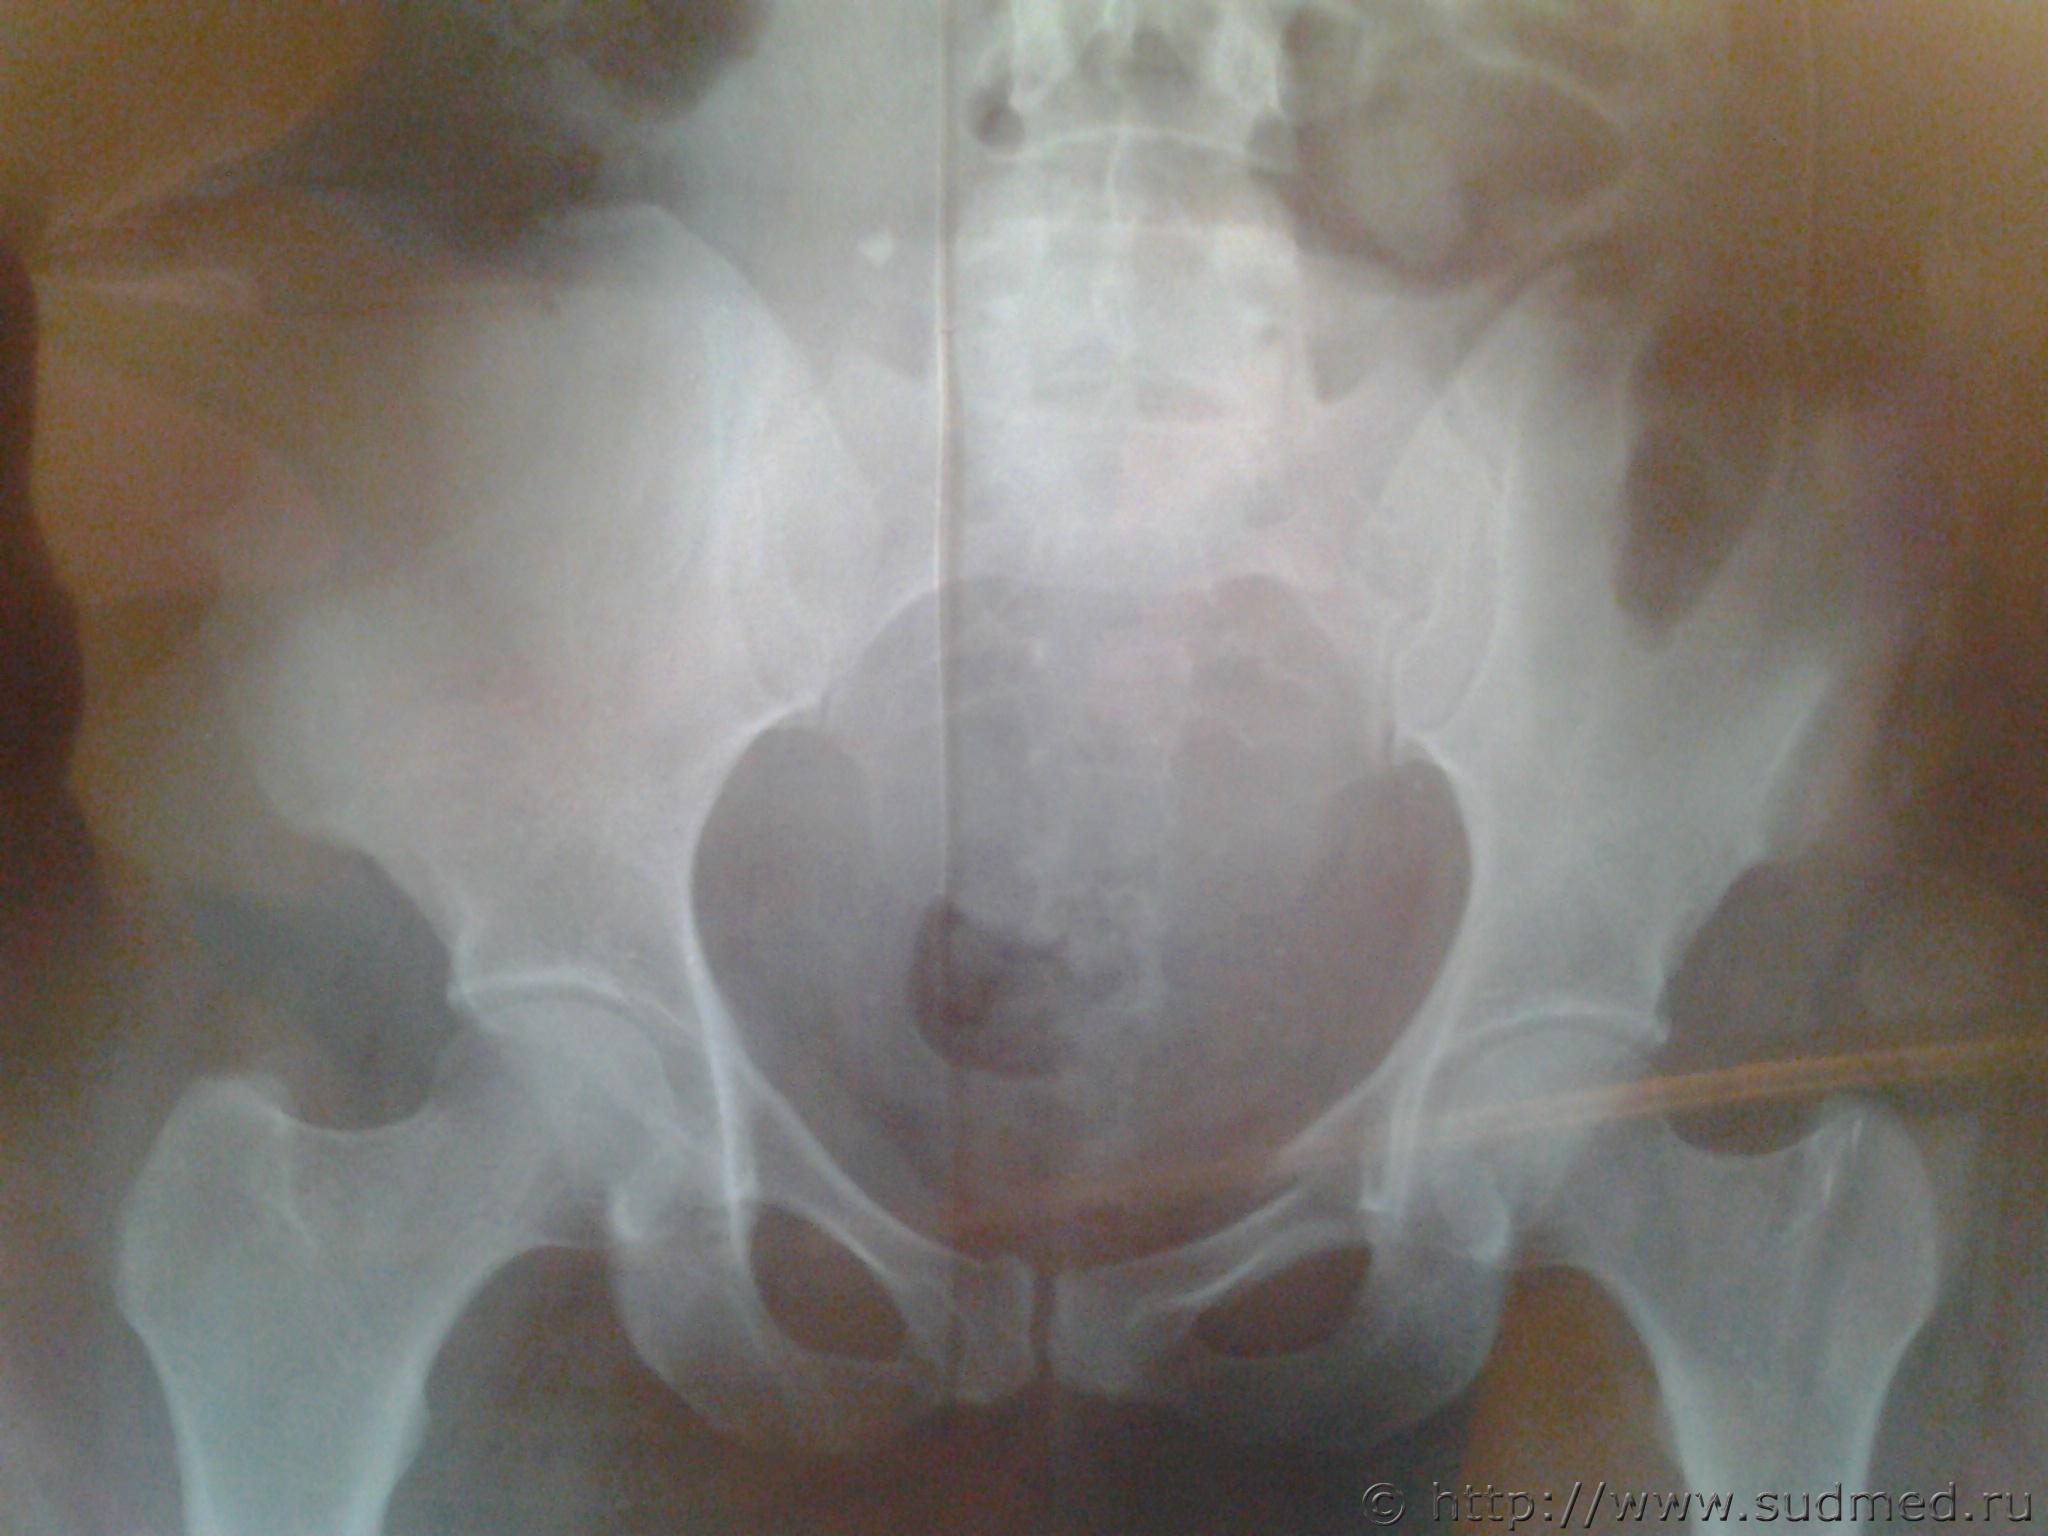

Закрытые оскольчатые переломы верхних ветвей лонных костей с обеих сторон. Закрытый краевой перелом лонной кости справа. Закрытый оскольчатый перелом боковых масс крестца слева.

По тому что видно на сканах перелом боковой массы крестца похож на полный вертикальный, но это одна точка нарушения тазового кольца для нестабильности и применения пункта 6.1.23 необходим еще один перерыв кольца, а на рентгенограммах и по вашему диагнозу переломы лонных костей без переломов седалищных. По представленной информации больше похоже на вред здоровью средней тяжести.

Предположений может быть только два. Дело не в количестве голосов "за" или "против". Ваши сканы качественно и количественно малопригодны для интерактива. Вы должны выяснить имеет ли место полный вертикальный перелом крестца или нет. Остальное - дело техники.